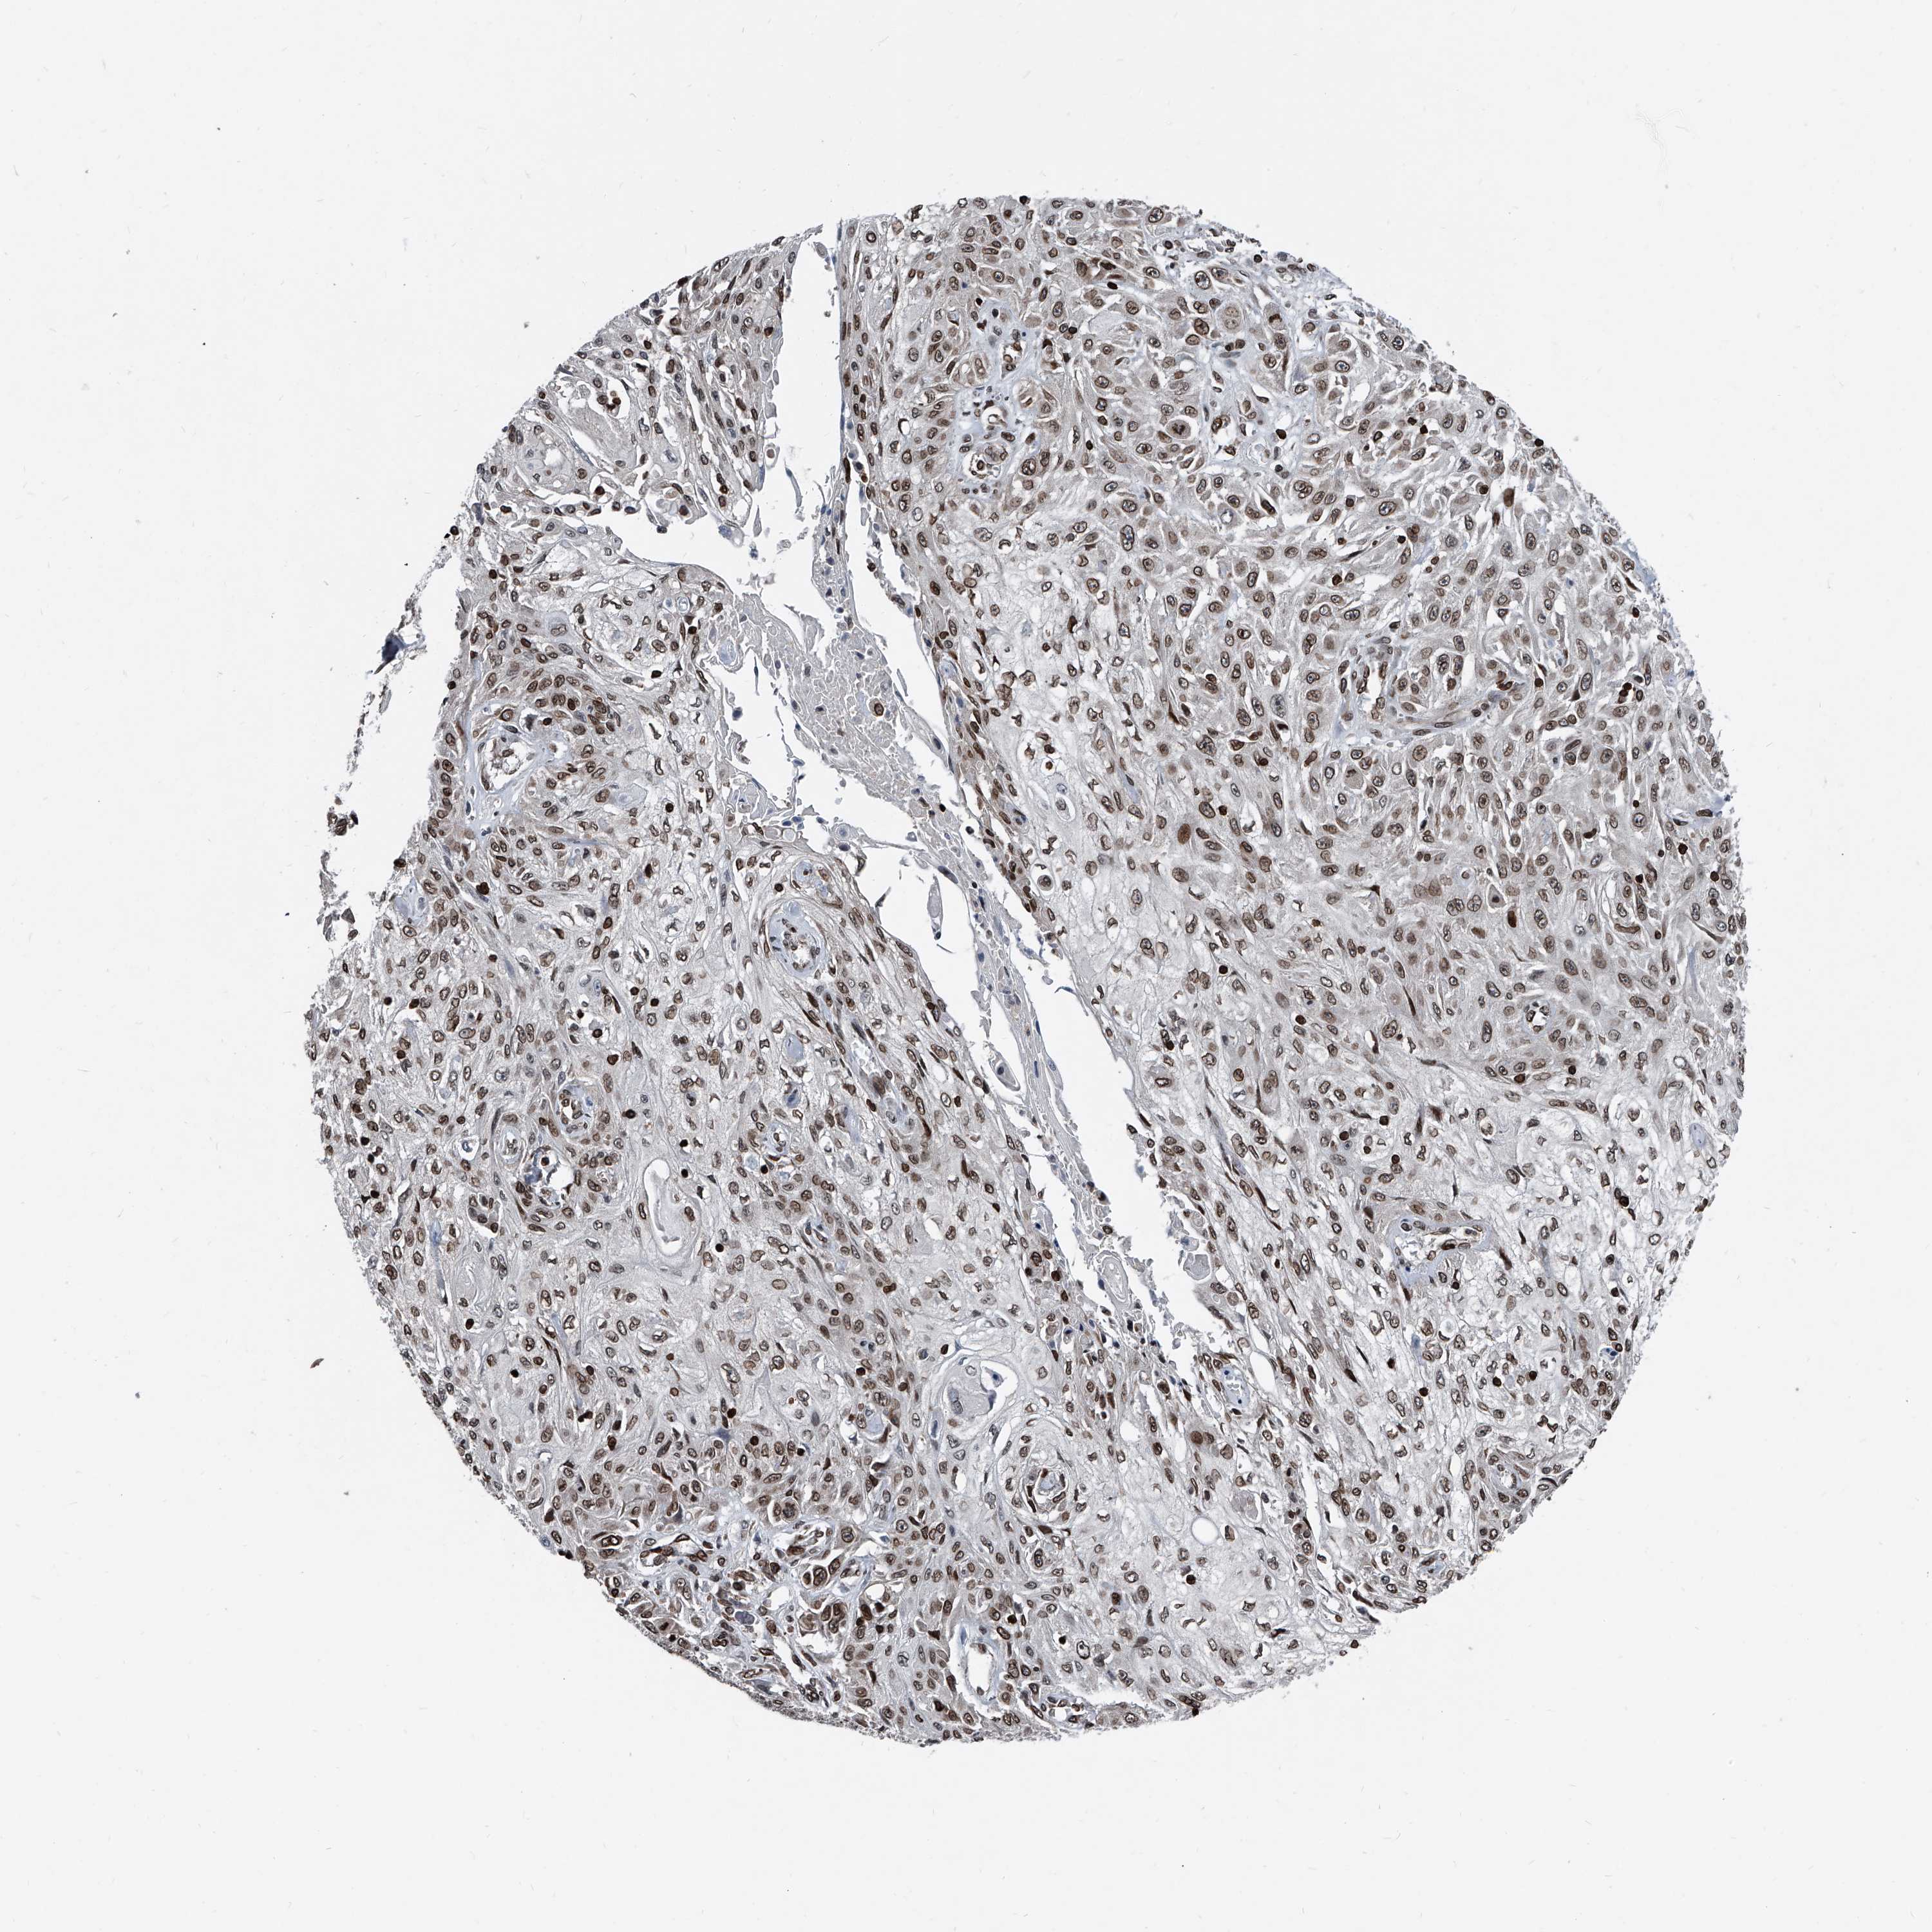

Basal cell and squamous cell cancer

SKIN CANCER - Protein expressioni

A mouse-over function shows sample information and annotation data. Click on an image to view it in a full screen mode. Samples can be filtered based on level of antibody staining by selecting one or several of the following categories: high, medium, low and not detected. The assay and annotation is described here.

Each image is clickable and will lead to virtual microscopy that enables deeper exploration of all samples and also displays staining intensity scores, fraction scores and subcellular localization as well as patient and tissue information for each sample.

Antibody HPA029621

Squamous cell carcinoma, NOS